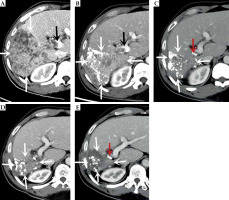

Fig. 2

Computed tomography (CT)-enhanced cross-sectional images of the portal phase before and after treatment. A) Before treatment. B) After more than 1 month of treatment. C) After more than 8 months of treatment. D) After more than 15 months of treatment. E) After more than 23 months of treatment. The white arrow indicate the gradually shrinking liver cancer lesion, the black arrow is the portal cancer thrombus, and the red arrow is the radioactive 125I particle

At follow-up date, February 24, 2020, the patient’s spirit and appetite had improved, and NRS score was 3. Enhanced CT showed a reduced lesion in the right lobe of the liver, but poor control of the portal vein cancer thrombus (Figure 2B). The overall assessment was that the lesion was well-controlled. After a multidisciplinary consultation and discussion, the patient underwent a minimally invasive 125I particle implantation intervention on February 26, 2020, with six 125I particles (average energy, 35.5 KeV per particle; half-life, 56 days; radioactivity, chemical 0.7 mCi; tissue penetration capacity, 1.7 cm). Based on pre-operative CT scans, the approximate dose distribution of solid tumors at the prescribed dose was simulated using treatment planning system (TPS, Beijing Hanglin Technology Development Co., Ltd., China), and the number and spatial distribution of particles (V100 ≥ 95% and D90 ≥ 100%) were determined by designing a linear array of radioactive particles in the center of cancer thrombus cross-section, extending along the long axis of cancerous thrombus (long axis of portal vein). Total irradiation dose was 120 Gy. Under ultrasound positioning, an 18 G eight-light needle was used to percutaneously puncture the center of cross-section of the cancerous thrombus, along the long axis of the right branch of parallel portal vein to 4 mm from the end of main stem of the cancerous thrombus. Radioactive particles were implanted continuously and linearly, with no space between particles. After implantation, the eight-light needle was left in place, and a CT scan of upper abdomen was performed for any possible sub-peritoneal bleeding, large vessels, and a particle displacement or gas embolism in the heart. After the particle implantation reached the expected plan, the eight-light needle was removed, pressure was used to stop the bleeding, and bandages were applied. Instruments used for this procedure included a pistol-type particle implantation device, an 18 G particle implantation needle, and 125I radioactive particles with an activity of 2.22E + 7 Bq (Beijing Atomic Technology Co., Ltd., China).

C-TACE was performed again on March 2, 2020, June 24, 2020, September 27, 2020, and December 17, 2020. The results of DSA hepatic arteriography showed that the right lobe of the liver was further reduced, and there was no arterio-venous fistula. The tumor-supplying artery was super-selected by microcatheter, and a chemotherapeutic solution was prepared by adding 50 mg of lobaplatin to 30 ml of 0.9% sodium chloride solution; chemotherapy was administering by infusion for 20 min via microcatheter. Pirarubicin 20 mg and iodized oil 10 ml was then used to prepare a suspension and embolized through the microcatheter, with additional gelatin sponge (diameter, 750-1,000 μm), until the tumor donor artery was completely embolized. The tumor was treated with oral anlotinib in a sequential manner. CT re-examination showed that the lesions in the liver gradually decreased, the portal vein gradually atrophied, a part of the portal vein opened, blood flow resumed, and the left lobe of the liver gradually increased. AFP level showed a continuous decrease (as of December 17, 2020).

On April 8, 2021 (after more than 15 months of treatment), the patient’s pain disappeared, NRS score was 3, his weight increased by 10 kg, and PS score was 0. CT results showed complete necrosis and no enhancement of the intra-hepatic lesion, atrophy of the portal vein, partial opening of the main trunk, and the right branch of the portal vein to restore blood flow (Figure 3). AFP level decreased to normal range (1.96 ng/ml). The patient returned to the hospital for follow-ups on July 28, 2021, December 26, 2021, July 25, 2022, and March 23, 2023, with no complaints of discomfort (PS score, 0). AFP values maintained within normal range, and CT results indicated no recurrence or metastasis. At the last follow-up on March 23, 2023, the patient had a pain NRS of 0, weight 68 kg, PS score 0, AFP 1.96 ng/ml, liver function Child-Pugh score 5 (human blood albumin 38 g/l, total bilirubin 6.2 μmol/l, PT 11.6 s, no ascites or hepatic encephalopathy). After extensive evaluation, the patient’s disease was completely controlled, with no long-term recurrence or metastases and radical outcome. To date, PFS is 37 months.